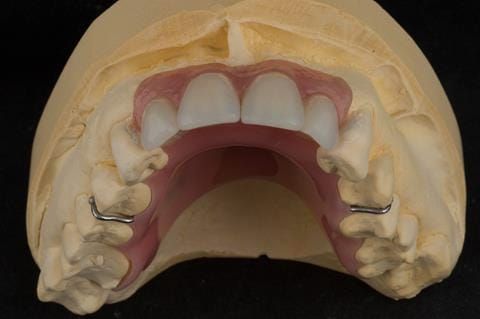

- Extract the upper 2-2 teeth and replace with an interim acrylic based partial denture. Reline the interim denture over 9 - 12 months, replacing with a definitive cobalt chromium based partial denture. The definitive denture would ideally be designed as an occlusal protective splint to reduce the the potential for mechanical wear and breakages of the moderately/heavily restored maxillary dentition. In addition, should further upper teeth require extraction they could be added on to the denture cobalt chromium framework - therefore a new prosthesis would not be required as future teeth are lost. This option would produce an excellent aesthetic outcome. This is the option the patient chose to have.

Following consultation and second discussion appointment the patient chose to have option 3 namely, a maxillary cobalt chromium based partial denture/protective occlusal splint. The clinical situation and treatment process is shown in detail below with photographs. The patient was successfully rehabilitated with this and her quality of life considerably improved. The clinical work was provided by Finlay and the technical work by Rowan.